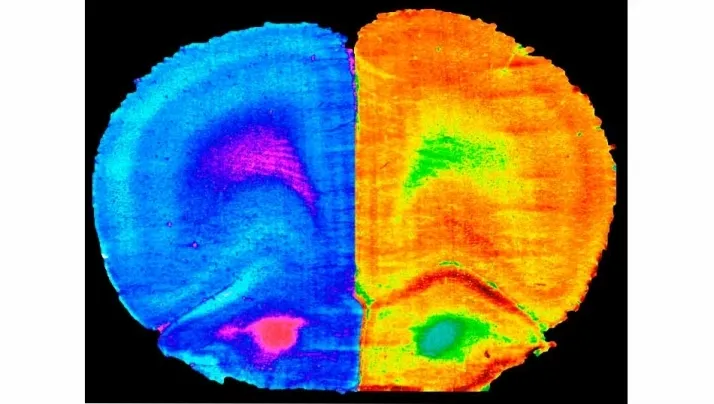

"Hemos descubierto que el deporte y la administración de 'A. muciniphila', no así la de 'L. rhamnosus GG', son capaces de revertir las alteraciones cognitivas asociadas a las dietas altas en grasa y colesterol causantes de numerosas enfermedades hepáticas. Nuestro trabajo ha conseguido una mejora cognitiva en los modelos animales que consumieron una dieta grasa. También hemos observado cambios en la actividad metabólica del cerebro y la composición microbiana intestinal, dos aspectos que habrá que seguir investigando para el diseño de futuras intervenciones en patologías inducidas por la dieta", destaca el investigador del CSIC.